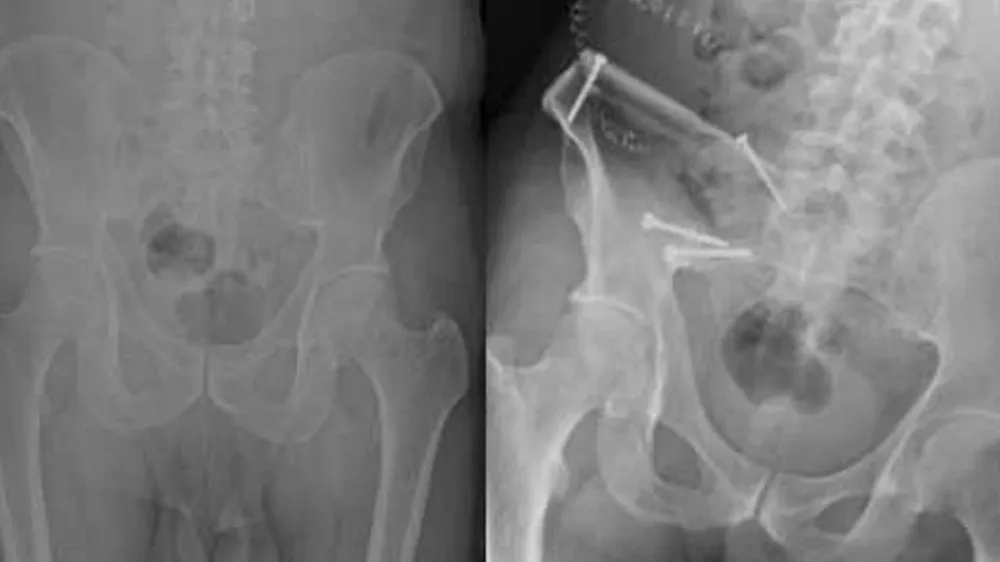

Prostat kanserinin ileri evrelerinde görülen kemik metastazları, iskelet sisteminde geri dönülemez hasarlara ve ani kırılmalara yol açtı. Uzmanlar, geçmeyen eklem ağrılarının kanserin yayılma belirtisi olabileceği konusunda kritik uyarılarda bulundu.

Kemik yapısını zayıflatan bu sürecin, geri dönülemez kırıklara ve hareket kısıtlılığına yol açabileceği kaydedildi.

New England Journal of Medicine'de yayımlanan geniş kapsamlı çalışmalar, prostat kanseri hücrelerinin kemik iliğindeki mikro çevreyle özel bir etkileşime girdiğini ortaya koydu. Bu etkileşim sonucunda kemiklerin normal yıkım ve yapım dengesinin bozulduğu, kemiğin yapısal bütünlüğünü kaybettiği belirlendi.

Metastatik prostat kanseri vakalarında görülen "patolojik kırıklar", hastaların yaşam kalitesini ciddi oranda düşürürken, tedavi süreçlerini de daha karmaşık hale getirdi.

Bono, "Kanser hücreleri kemiğe ulaştığında, kemiği içeriden zayıflatan bir süreç başlar. Hastalar genellikle bu durumu ciddi bir kırık yaşayana kadar fark etmeyebilirler. Bu nedenle, prostat kanseri geçmişi olan bireylerde iskelet sistemi hassasiyetle takip edilmelidir" şeklinde görüş bildirdi.